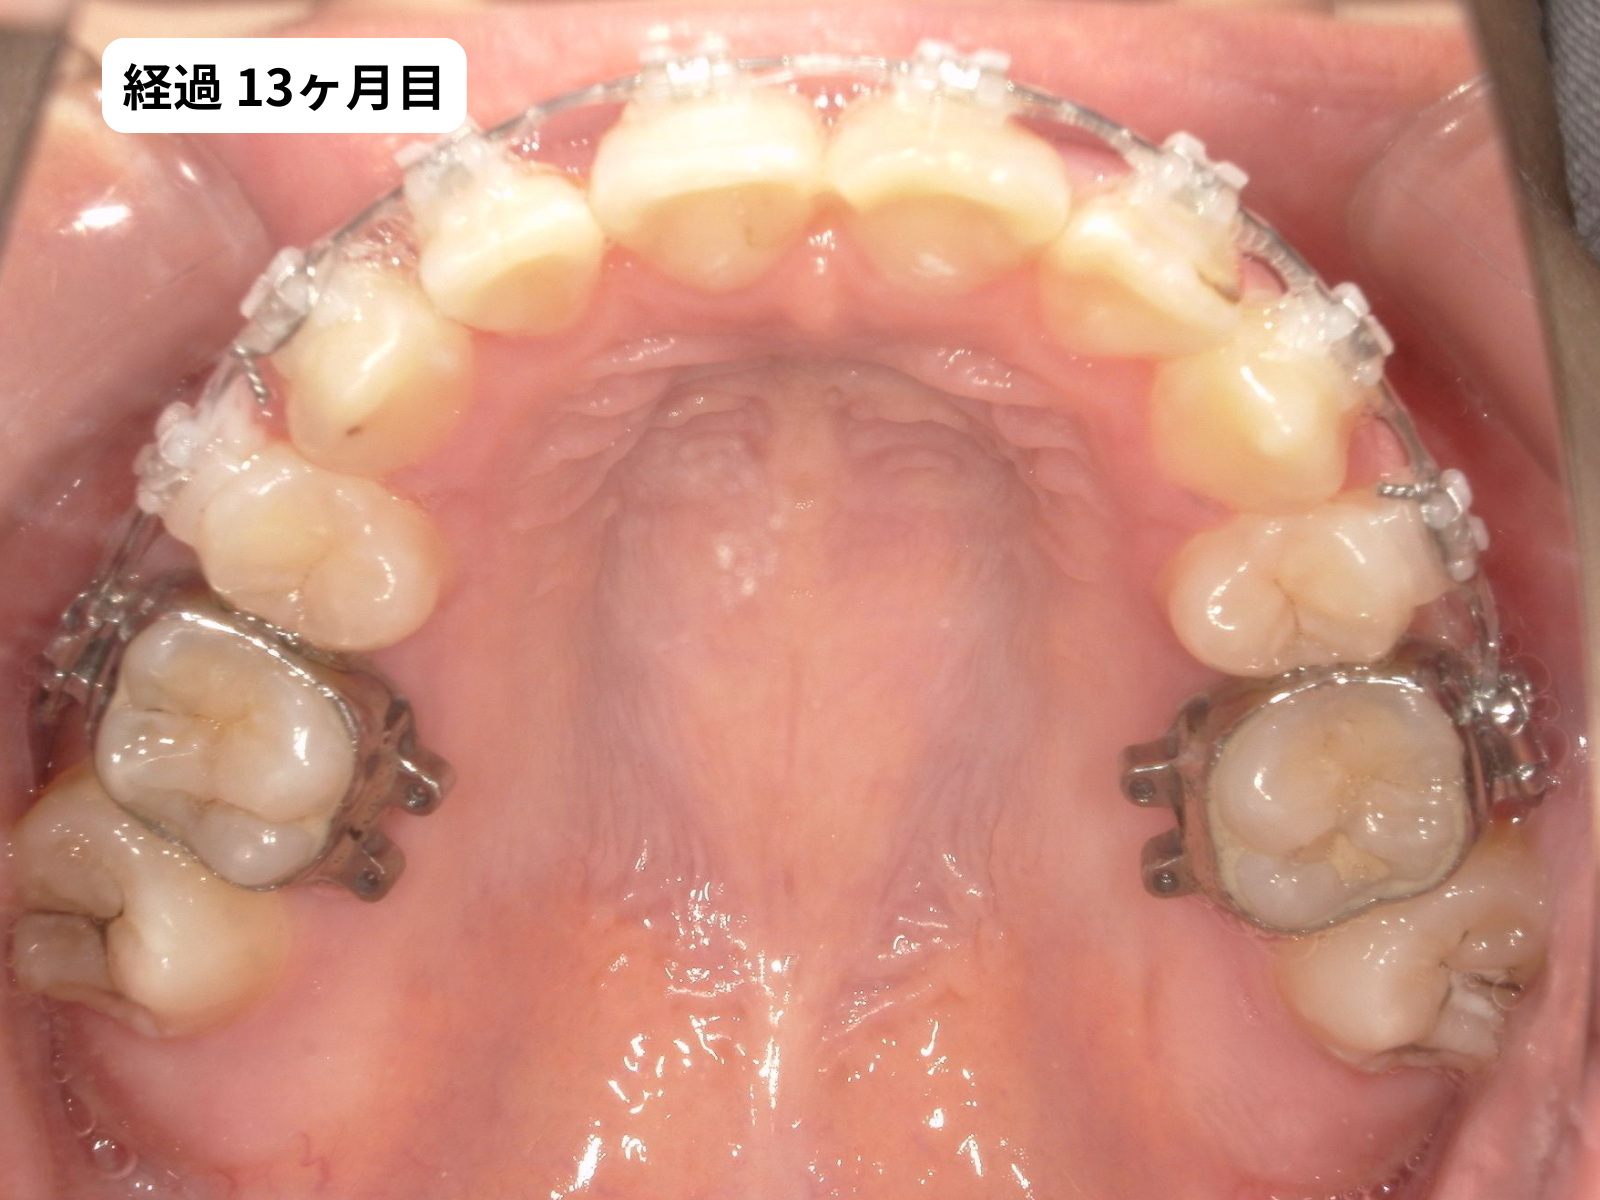

装置装着から1年2ヶ月、毎月の経過

装置をつけた後、上の歯の噛み合わせ面の写真を毎月記録しました。下のスライダーで、月ごとに歯がどう動いていったかをご覧いただけます。

毎月の写真で歯がスムーズに動いているのがわかります。これは 軽い力(約50g)でゆっくり動かす、毎回の来院で移動距離を確認する、この2つを積み重ねた結果です。